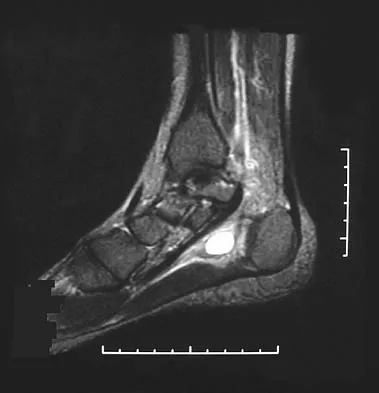

Test your knowledge with updated Orthopedic MCQs for 2026. Perfect for board exam preparation, FRCS, and Prometric test practice.